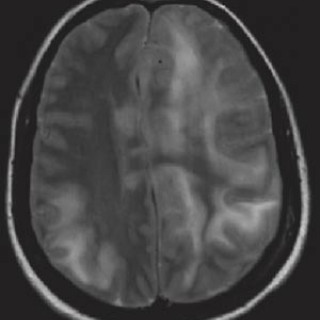

En 23 år gammel førstegangsgravid kvinne som fra tidligere stort sett var frisk, ble innlagt i lokalsykehus ved svangerskapslengde 22 uker + 2 dager, med en seks dagers sykehistorie med generell sykdomsfølelse, feber opptil 40 °C, kvalme, oppkast og anoreksi. I tillegg hadde hun fått økende ansiktsødemer, korsryggssmerter, hodepine og synsforstyrrelser. Svangerskapet hadde vært ukomplisert frem til det aktuelle. Hun var normotensiv. Blodprøvene viste kreatinin 236 µmol/l, karbamid 13 mmol/l, urat 410 µmol/l, leukocytter 15,0 · 10⁹/l, CRP 106 mg/l og trombocytter 86 · 10⁹/l. Leverprøvene var...